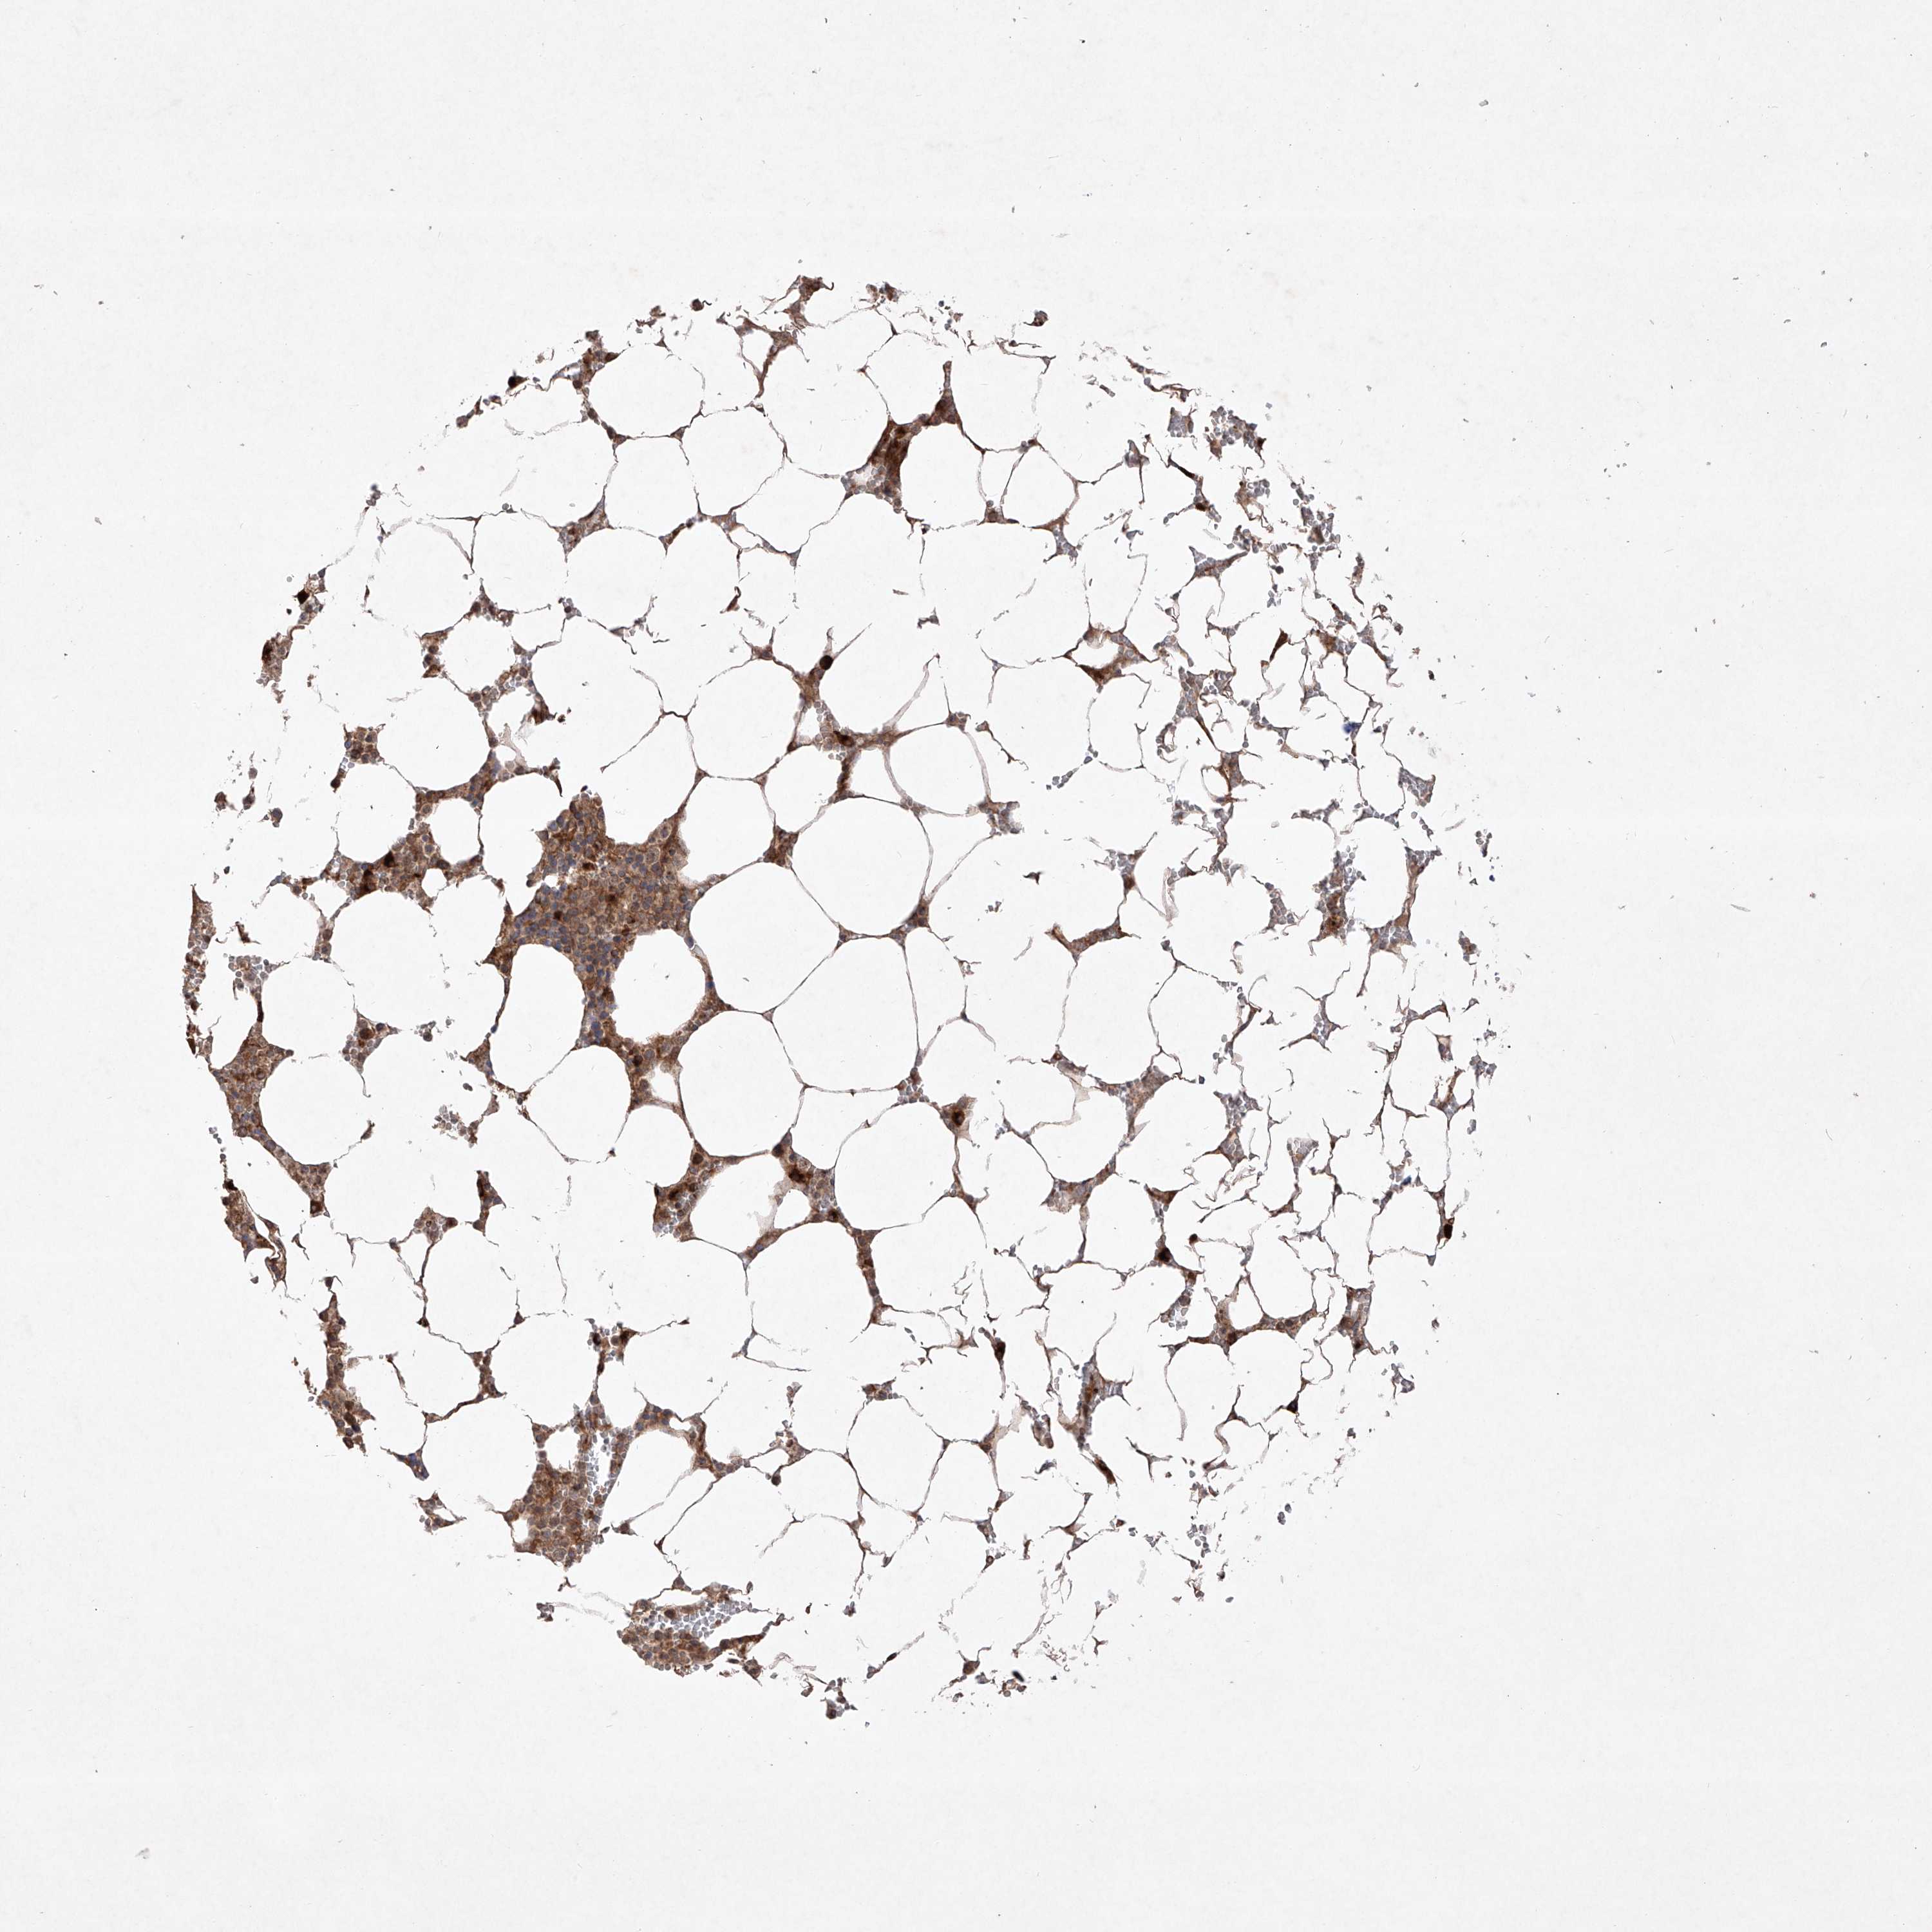

BONE MARROW - Antibody stainingi

Antibody staining in the annotated cell types in the current human tissue is reported as not detected, low, medium, or high, based on conventional immunohistochemistry profiling in selected tissues. This score is based on the combination of the staining intensity and fraction of stained cells.

Each image is clickable and will lead to virtual microscopy that enables deeper exploration of all samples and also displays staining intensity scores, fraction scores and subcellular localization as well as patient and tissue information for each sample.

Antibody HPA030817Antibody HPA030818

Hematopoietic cells MediumLow